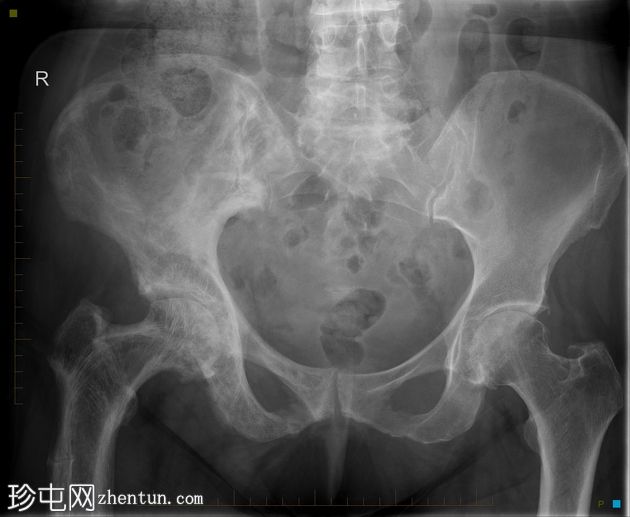

患者因跌倒后出现右髋

。

年龄:80岁

性别:女

X线片

正位片

显示右侧股骨近端香蕉状骨折,伴右侧股骨和髋臼广泛性佩吉特病。

本病例展示了右侧髋关节和股骨广泛性佩吉特病继发的香蕉状骨折的典型特征,经右侧骨盆和髋关节X线及CT检查证实。